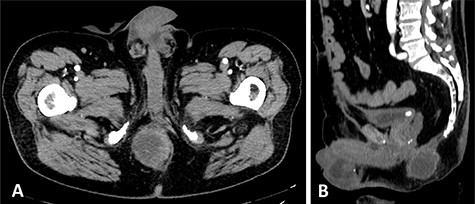

After a multidisciplinary consult, an adjuvant chemotherapy and pelvic radiotherapy treatment was proposed to the patient, but he refused and avoided to undergo oncological follow-up until October 2019 when he noticed the appearance of a hard-wooden swelling in the soft tissue of right perineal region (6–7 cm in diameter). After a CT scan (Fig. 1) and MRI that confirmed a local recurrence of cancer, following a multidisciplinary discussion between surgeons, radiation oncologists, radiologists and oncologists, a surgical resection indication was given.

Preoperative CT that documents the absence of a clear cleavage plane between the neoplasm and the urethra in axial (A) and sagittal (B) scans.

However, the CT investigation documented a close relationship between the neoplastic lesion and the root of penis and urethra, with consequent difficulty in obtaining the certainty of disease-free margins without a major demolition procedure that the patient firmly refused.